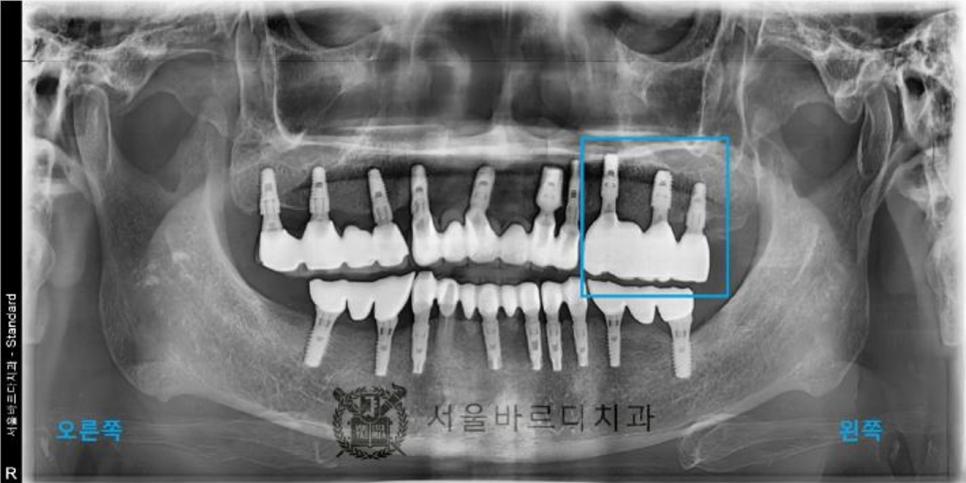

파노라마 엑스레이 촬영 후 검사 결과 전체적으로

잇몸이 많이 내려가신 상태이고

안 좋은 곳들이 많이 있었고,

20년 전에 치료하신 치아들이라 보철물도

여기 저기 많이 깨져있었습니다.

사진상으로도 뼈소실이 많이 있었고,

심하게 흔들리는 상태이셨는데 자연적으로 빠지셨습니다.

앞에 임플란트(작은 어금니)의 뿌리 부분의 뼈가 염증으로 녹아

더 이상 임플란트가 뼈에 박혀 있을 수 없어서

뒤 보철물과 함께 빠진 경우입니다.

그나마 끝 어금니(큰어금니)가 잡아주고 있어서

지금까지 사용이 가능했으나

끝 어금니 임플란트의 나사가 풀리면서

보철물이 빠지게 된 것입니다..

임플란트 후에도 수술이 잘 되었는지

파노라마와 3D CT촬영으로 결과를 확인합니다.